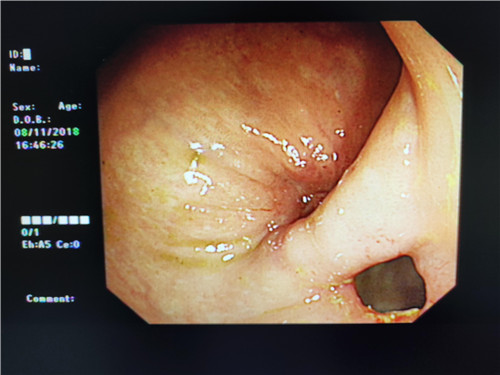

在检查过程中,当曹鹏主治医师将内镜进至吻合口狭窄处时,却偶然发现狭窄部位旁边还有一小小入口,探镜而入,发现这条小小隧道与狭窄部一同通向肠腔,中间相隔了一条不宽不窄的“桥梁”,把本来通畅的“大路”隔成了两条幽径小道,因此患者排便才会堵塞不通。经过反复观察,仔细斟酌后曹鹏医生萌生了,把“桥梁”拆掉,使“曲径小路”变“宽敞大道”的想法。因为这时如果按原计划行肠镜下吻合口扩张术已经没有太大的意义,但肠道薄弱容易造成穿孔,“桥梁”处是否有大的血管,存在出血、穿孔的风险等等,这些都需要与主管医生进一步探讨。随即他与普通外科史和平主任,消化内镜室王莹主任会诊后决定实施“粘膜桥离断术”(ESD内镜下粘膜剥离术)。将术中风险及意外向患者及家属充分告知后,征得患者家属同意签字,随后便开始施行手术。在史主任、王主任、李侠护士长的支持保驾护航之下,曹鹏医生以精湛的医疗技术,与护士的默契配合,顺利完成了手术,术中无出血、穿孔,眼前显示器屏幕上出现了预期中的“宽敞大道”,手术成功了!大家原本绷紧的面容出现了笑容。患者从此以后不会再有排便不畅的痛苦了,患者唐某及家属,欣喜及感激之情溢于言表,医生们再一次为他解决了一件大事情,患者术后恢复良好。